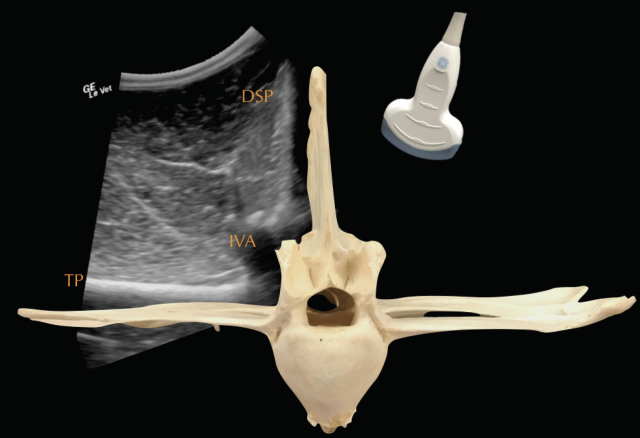

• Ultrasonography of the back should be combined with the radiographic examination and is particularly useful to examine superficial soft-tissue structures and the intervertebral articulations. To assess all structures of interest, both linear and convex transducers are required.

Deep to the ligament the fibrocartilaginous cap, visualised as a hypoechogenic line of approximately 1mm, is visible and runs parallel to the hyperechoic line of the DSP bone surface. The ISS cannot be assessed fully and a statement about potential iminging DSPs should not be made based on ultrasonography alone. The intervertebral articulations can be examined ultrasonographically, both in sagittal and frontal planes, using a convex transducer (Denoix 1999a; Reisinger and Stanek 2005).

The anatomy and ultrasonographic appearance of the joints change slightly from cranial to caudal. The mammillary process is more prominent in the thoracic spine and the joint is positioned further axial and closer to the DSP compared to the lumbar region. Signs of pathology in the intervertebral articulations (see Figure 4) include new bone formation and an enlarged outline of the facet (Denoix and Dyson 2003).